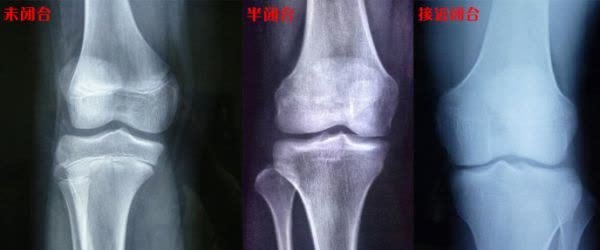

来到医院检查,医生检查了玮玮的骨骼,没啥问题,还有较大的发育空间,医生建议去儿科检查一下伟伟的脾胃情况。